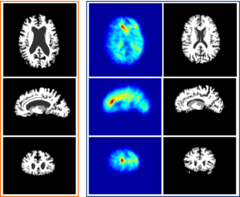

Results from the new implementation are:

Design ITK classes for Hierarchical Attribute Matching Mechanism for Elastic Registration (HAMMER) and White Matter Lesion segmentation so that these algorithms can be easily implemented using the Insight Toolkit and integrated into Slicer. The goals of the week is to analyze the algorithms on the object level, map components to existing ITK classes, identify gaps, and start implementation. Will also identify testing dataset and generate baseline results for testing.

- Dinggang Shen, Christos Davatzikos, HAMMER: Hierarchical Attribute Matching Mechanism for Elastic Registration, IEEE Trans. on Medical Imaging, 21(11):1421-1439, Nov 2002.